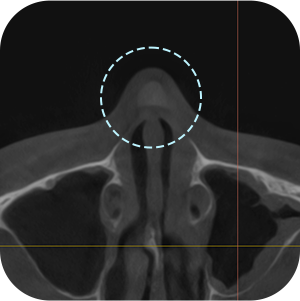

确认之前手术 的假体情报

确认鼻中隔弯曲症等 功能性问题

确认目前现假体 的位置

一定要拍鼻子CT吗?

A因为是修复手术,所以要更精密地诊断!

鼻部修复手术需要彻底的分析非常重要

通过3D-CT扫描 准确的分析! - 03